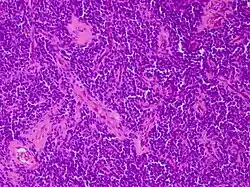

Für PNET typische Histopathologie: ein klein- rund- und blauzelliger Tumor. Hämatoxylin-Eosin-Färbung. Vergrößerung 200x

Die richtungsweisende Diagnostik erfolgt zumeist über eine feingewebliche (histologische) Untersuchung nach Probeentnahme (Biopsie) oder Entfernung des PNET (Resektion durch Operation). Letztere kann insbesondere bei PNET im Zentralnervensystem nur teilweise oder gar nicht möglich sein.